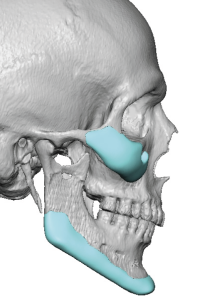

Custom designed or 3D jaw implants are the contemporary workhorse in lower facial asymmetry corrections. With modern patient-specific CT-based implant designing virtual planning an be done to design different right and left dimensions, matching the right and left sides of the jawline and centering the chain can be done far more accurately than stock implants ever could. 3D imaging is important because facial asymmetry is a true 3D problem and standard 2D assessment, even with plain x-rays and 2D CT scans, can not fully appreciate the extent of the asymmetries down to the millimeter level.

- Facial asymmetry is a multi-dimensional hard and softC tissue problem whose contemporary treatment requires 3D assessment and treatment planning.

- Most jaw asymmetries are best treated by a wrap around jawline implant approach to manage the bilateral deformities.

- Cheek flatness/hypoplasia is almost always part of a significant jaw asymmetry.